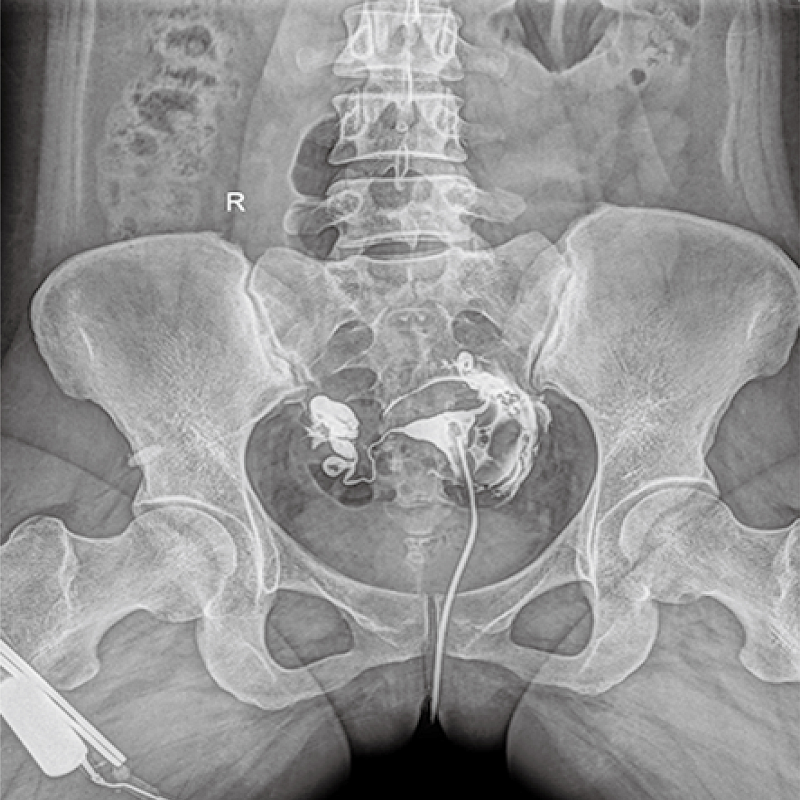

多功能、全視角、真視界,全面突破傳統X線攝影透視理念,通過一塊新型動態平板探測器,在檢查中既可實現數字透視又可實現數字攝影,還可做數字胃腸及數字造影檢查。

● 只需一塊動態平板探測器,高效輕松實現攝影、透視和造影功能,幾乎可以滿足醫院全科室